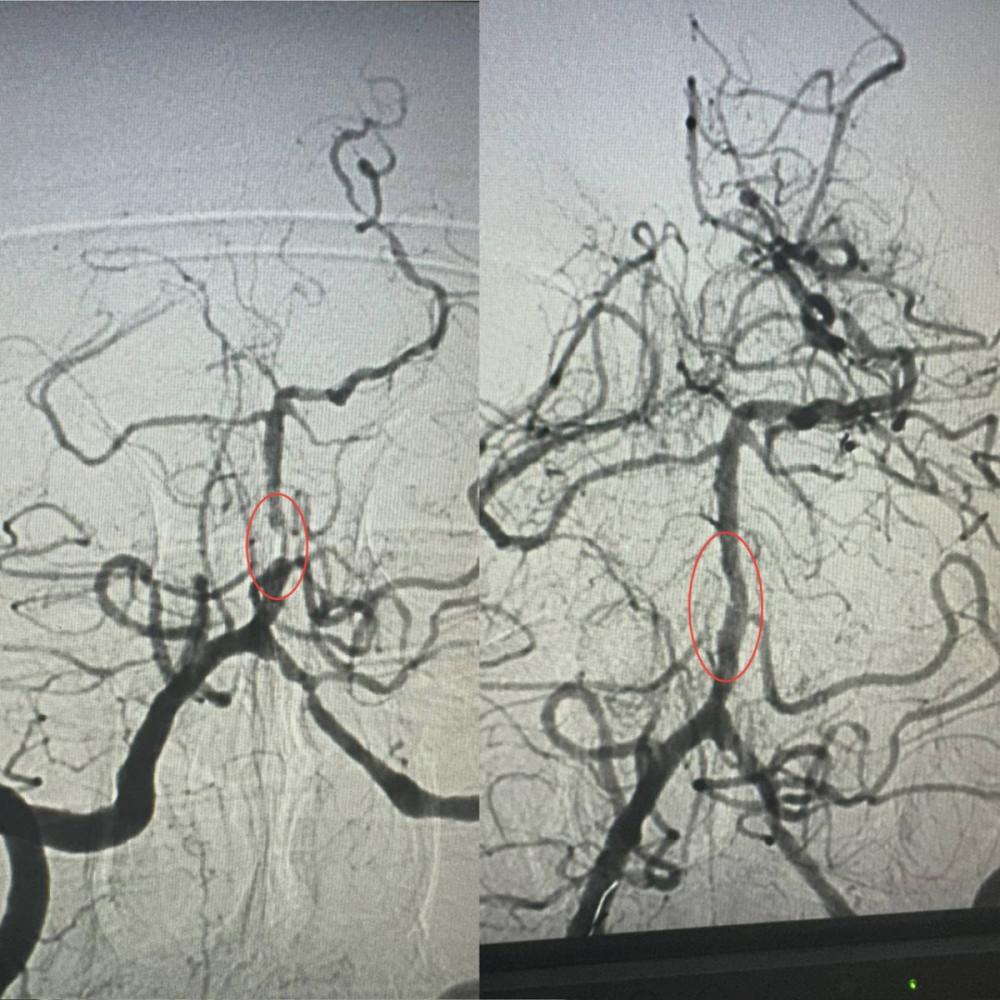

Завідувач рентгенендоваскулярного відділення Олександр Скрипка повідомив, що це був один з найскладніших випадків - ураження стовбура мозку. Базилярна артерія була практично повністю заблокована атеросклерозом. Такі інсульти є надзвичайно небезпечними, а без термінового втручання шанси на виживання практично зникають.

Лікарі вирішили провести операцію з ангіопластики артерії. Лікарня №10 має досвід у цій методиці для лікування коронарних артерій, але її використання для артерій мозку є новаторським підходом в Україні.

Операція тривала близько години. Звужену артерію розширили за допомогою спеціального балона, а потім використали балон з лікарським покриттям.